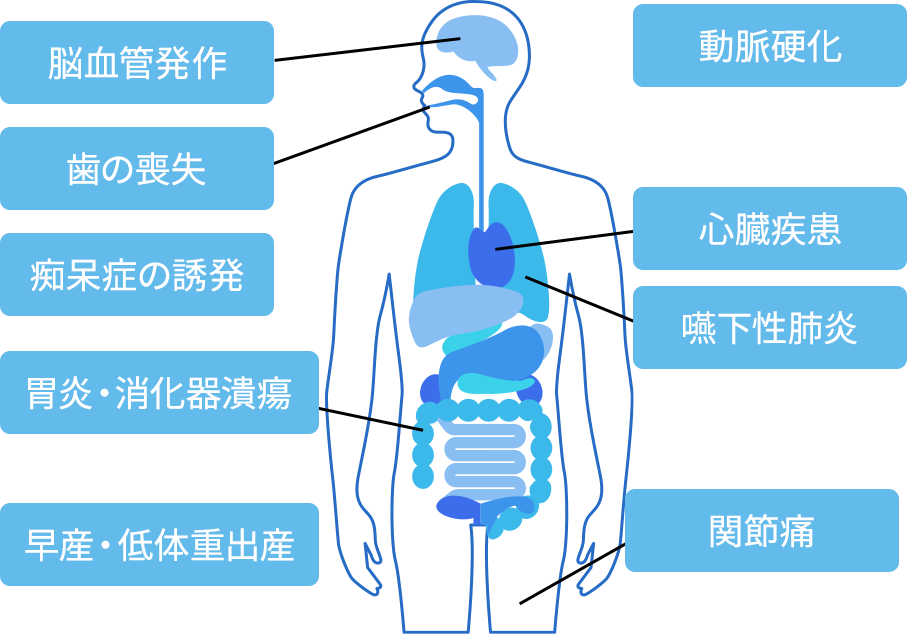

口腔内で繁殖した歯周病菌は、歯周組織を溶かし、歯を失うリスクを伴いますが、それだけでなく、感染部分から血液にまで細菌が流れることで全身の病気へ影響を及ぼします。

口腔内の歯周病菌を減らすことにより、お口の中から全身の健康を守ります。